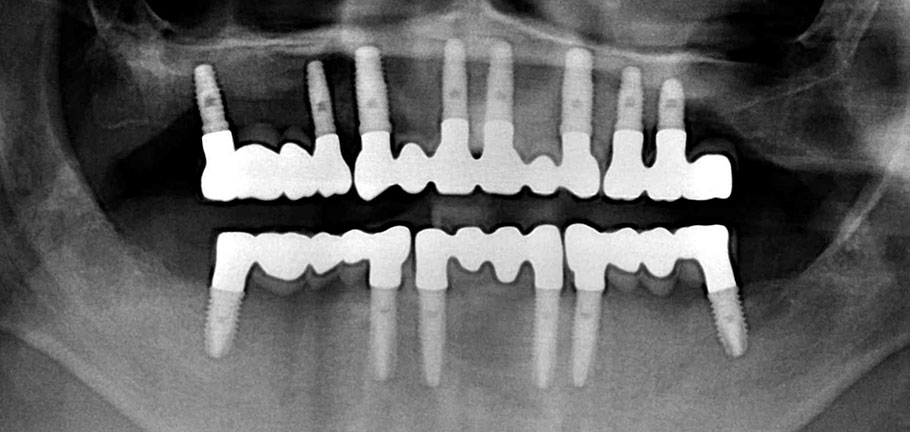

Los implantes dentales son unas piezas de titanio que se colocan en los maxilares para reponer dientes perdidos, actuando como raices artificiales.

Los implantes son la mayoría de los casos la mejor solución para reponer piezas ausentes preservando la integridad de los dientes vecinos, aportando al paciente COMODIDAD, CONFIANZA Y AUTOESTIMA.

Como norma general el tiempo de espera desde la colocacón del implante hasta la realización de la prótesis suele ser de 8 semanas que tarda el implante en integrarse en el hueso.

En muchas ocasiones cuando la estética está comprometida, pueden realizarse dientes fijos implantosoportados provisionales el mismo día de la cirugía, que además nos ayudan a conformar los tejidos blandos, dando al paciente un mayor confort y estética desde el primer momento.